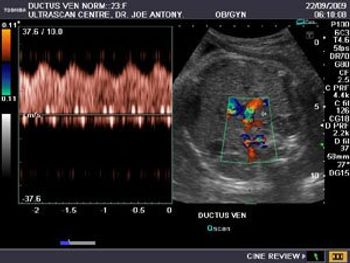

Normal 35 week pregnancy